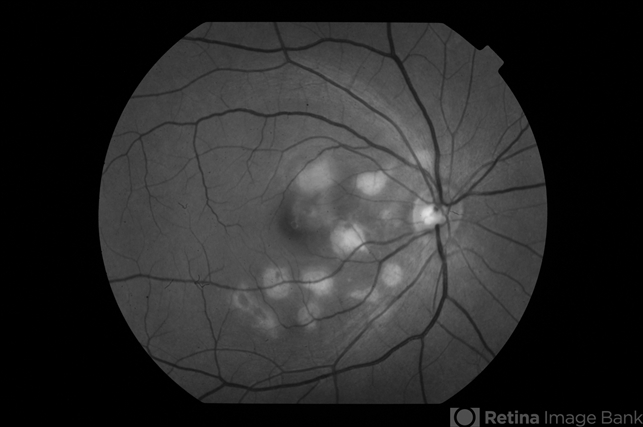

- Serpiginous Choroiditis

- serpiginous choroiditis, macula serpiginous choroidopathy, white dot syndrome, acute posterior multifocal placoid pigment epitheliopathy (APMPPE)

- Dr Haider Ali Chaudhry, Madinah Teaching Hospital, Faisalabad

- Fundus camera

- 35-year-old female presented with decrease in vision in her left eye for last 4 days and in right eye for last 8 days. Her right eye was previously involved in a similar episode about 5-6 months ago for which she was treated with oral steroids.